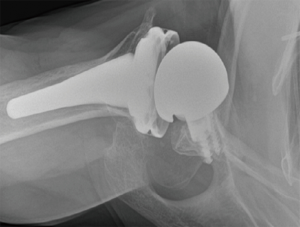

Prosthetic malalignment (Figure 2) can cause dislocation of RSA if excessive anterior version of the glenosphere and/or excessive retroversion of the humeral component, resulting in abutment of the humerosocket against the glenoid neck during internal rotation (3,6,12,15,25,34). However, it is still unclear how much misalignment of the component can be considered a risk to RSA stability.

In a level III study, Tashjian et al. analyzed 168 RSAs with 13% of instability found the only risk factor significantly associated with instability was the superior inclination of the baseplate after controlling for age, sex, body mass index, and primary versus revision procedure (24). This fact emphasizes the importance of preoperative planning and meticulous placement of the baseplate. Inclination of the glenoid can be reliably measured on true anteroposterior radiographs of the shoulder joint using the beta-angle described by Maurer et al. (39). Given that the correct position of the baseplate occupies the inferior two thirds of the glenoid, recently Daggett et al. proposed a modification to this measurement called the “reverse shoulder angle” to avoid underestimation of glenoid inclination (40) (Figure 3). Although 15º of inferior tilt of the baseplate was demonstrated to be associated with decreased rates of glenoid loosening and failure (2,16), further studies are necessary to correlate baseplate inclination with instability risk.